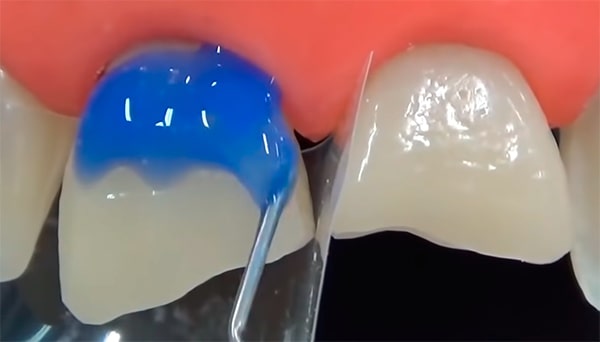

Что делать, если откололся кусок зуба: советы и рекомендации

Раздел: Необычные решения